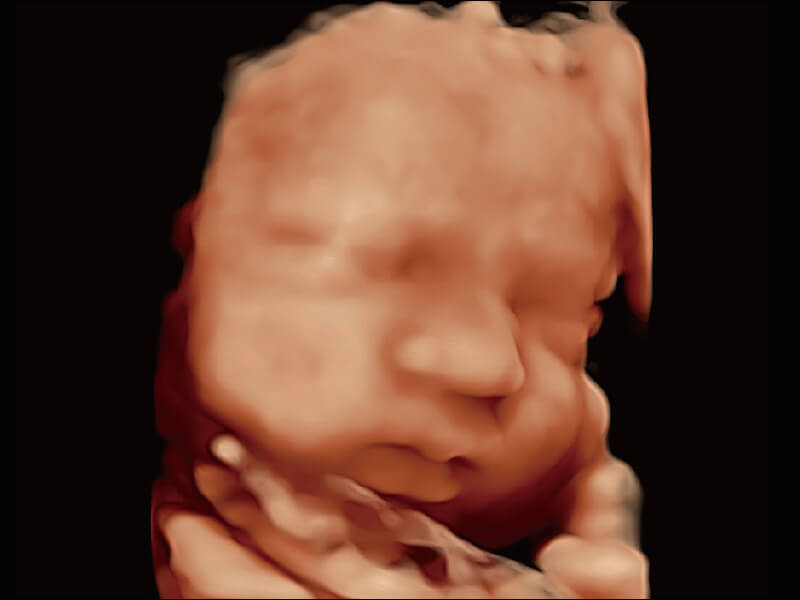

创新的超宽频带技术,为容积成像带来优质的二维图像基础,为您呈现更丰富的结构细节,栩栩如生地展示宝宝的宫内形态以及各种组织的立体结构。